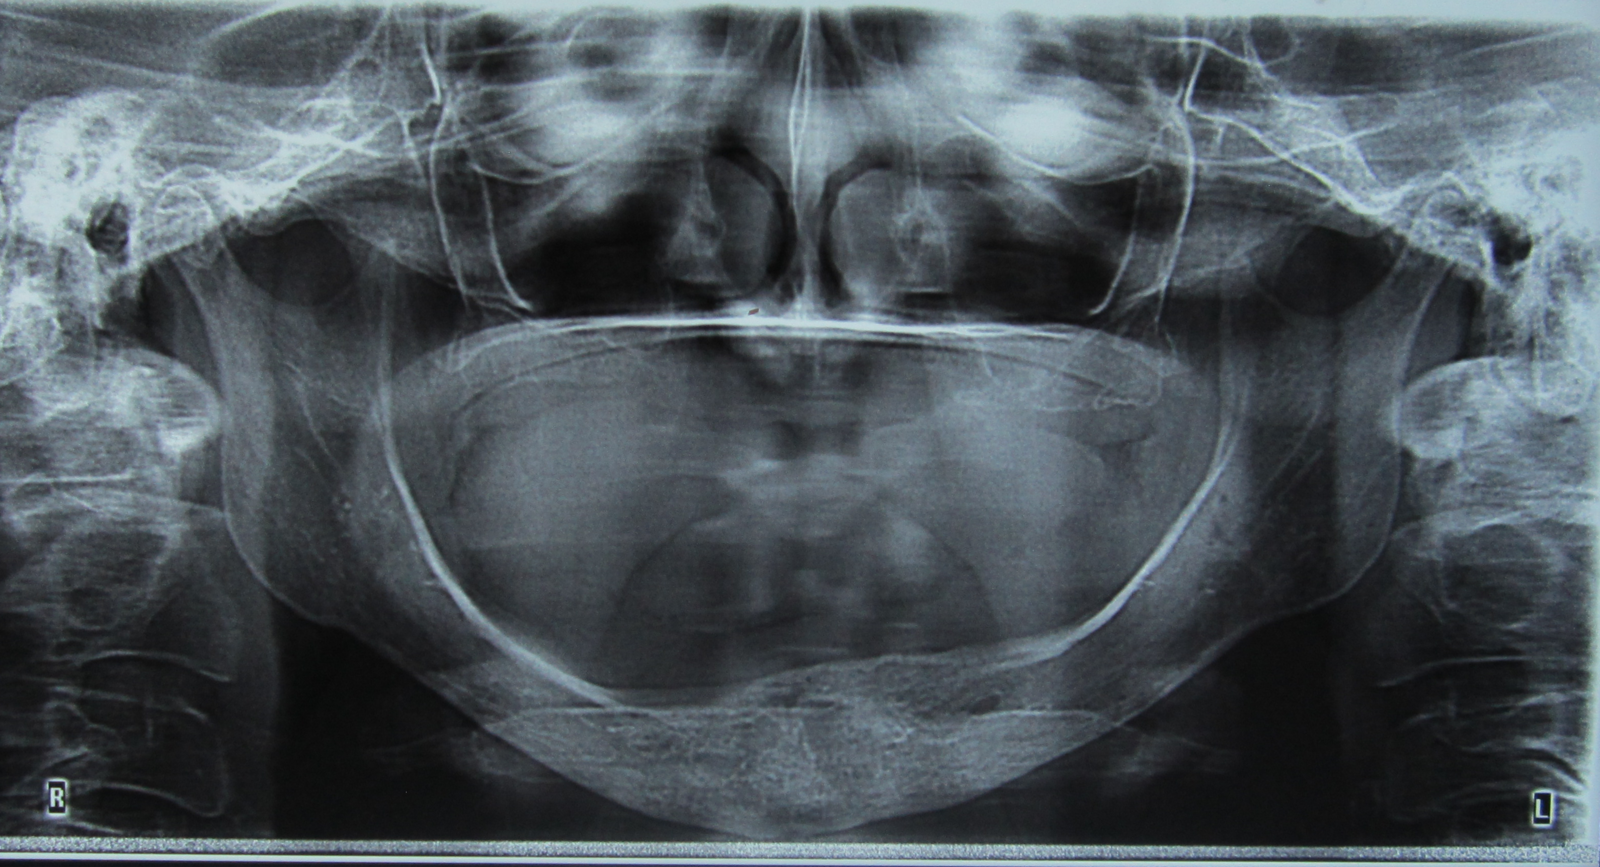

Radiografía panorámica

Julio 5 de 2014

AYUDAS DIAGNÓSTICAS